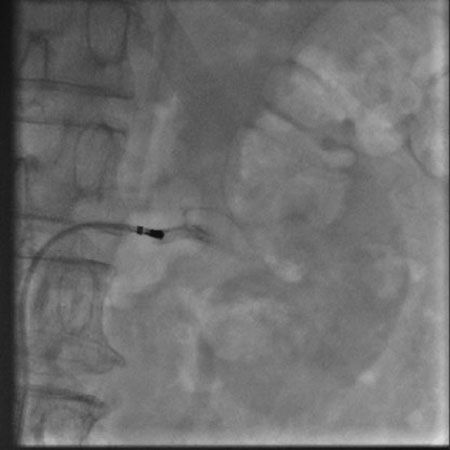

肾动脉造影(左)

肾动脉造影(左) 2月6日,我院心内科在上海普陀区中心医院心内科刘宗军主任指导下开展了我省首例肾动脉交感神经射频消融术。目前患者病情稳定,一周后复查动态血压,平均收缩压已从术前157mmHg降至137mmHg,患者已出院在继续随访中。 肾动脉交感神经射频消融术用于难治性高血压的治疗,于2008年在美国首先应用于临床,属介入手术,只需穿刺肾动脉进行手术,治疗完成后1—3月内患者血压即可明显下降,最大降幅可达30—40mmHg。术后患者服用少量降压药物即可将血压控制在良好水平,部分患者可以永久摆脱降压药物。从而避免了终生服用降压药带来的经济负担、生活不便和副作用影响。 心内科此次开展的肾动脉交感神经射频消融术在我省还属首例。目前国内仅北京、重庆、上海等少数医院开展该项手术。 高血压是最常见的心血管疾病,其中顽固性高血压患病率为5%-30%。肾动脉交感神经射频消融术的开展,对于提高高血压的控制率,减少和延缓并发症的发生具有重大意义,是近年来心血管领域最重要的进展之一。该手术的开展,属国内先进、省内领先的行列。(心内科 李燕萍 郝应禄) |